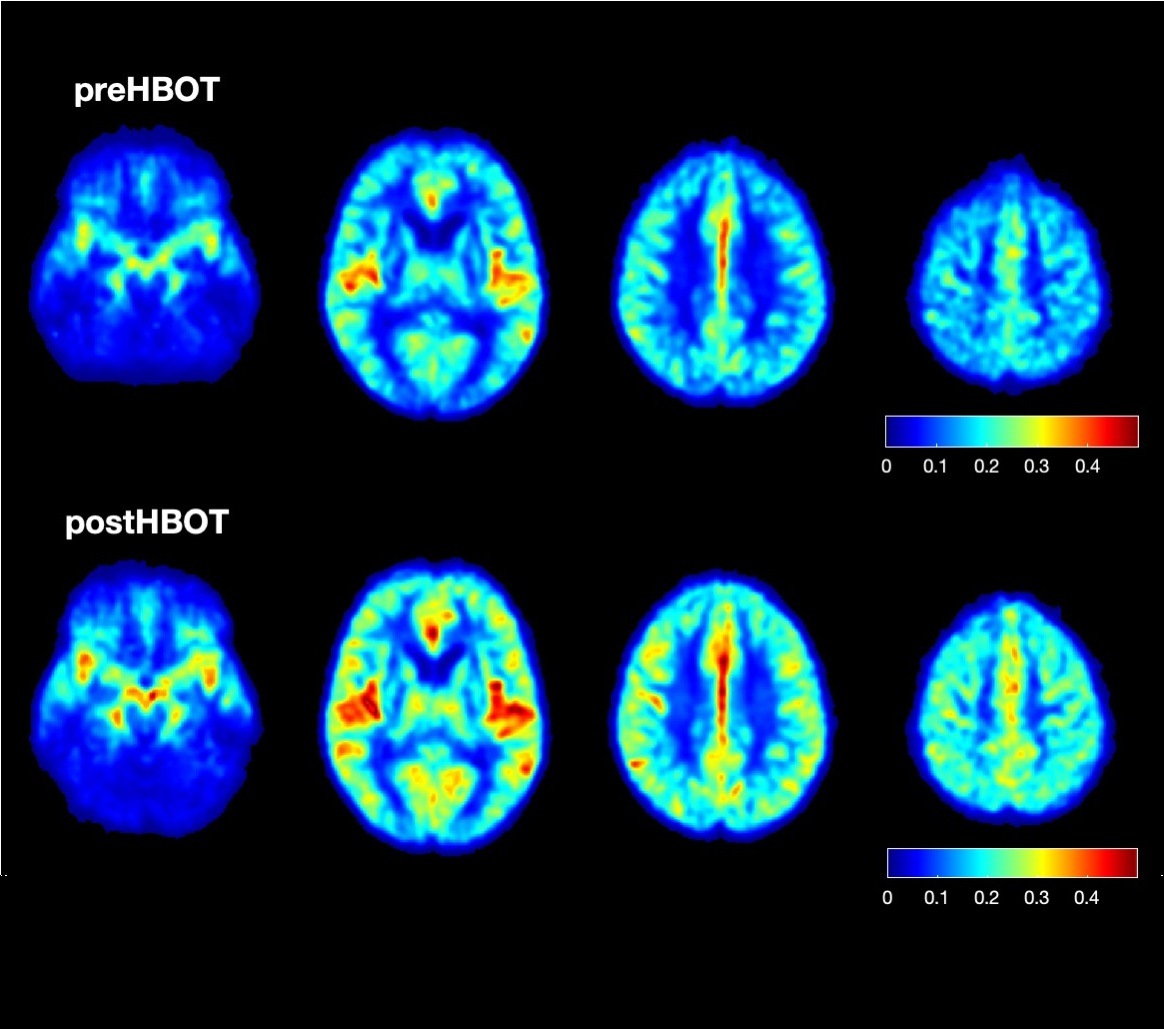

hbot thumbnail